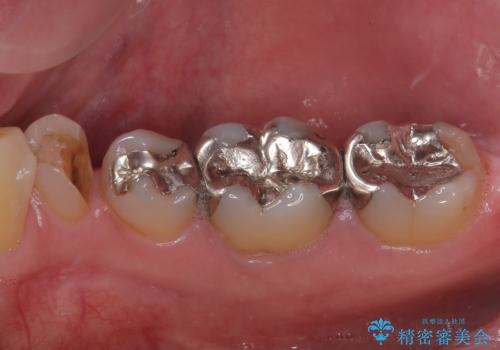

- 右下の銀歯が取れたとのことで来院された患者様です。以前にも取れていたところで、メタルインレーの不適合も認めていたため、次回外れたらオールセラミッククラウンにやり替えていくことを説明していたため、オールセラミッククラウンによる補綴治療を行っていくことにしました。

拡大鏡視野下で虫歯を除去しオールセラミッククラウンに適した形に整えました。

歯と歯茎の間に圧排糸と言われる糸を入れてシリコーン印象材にて型どりをしました。